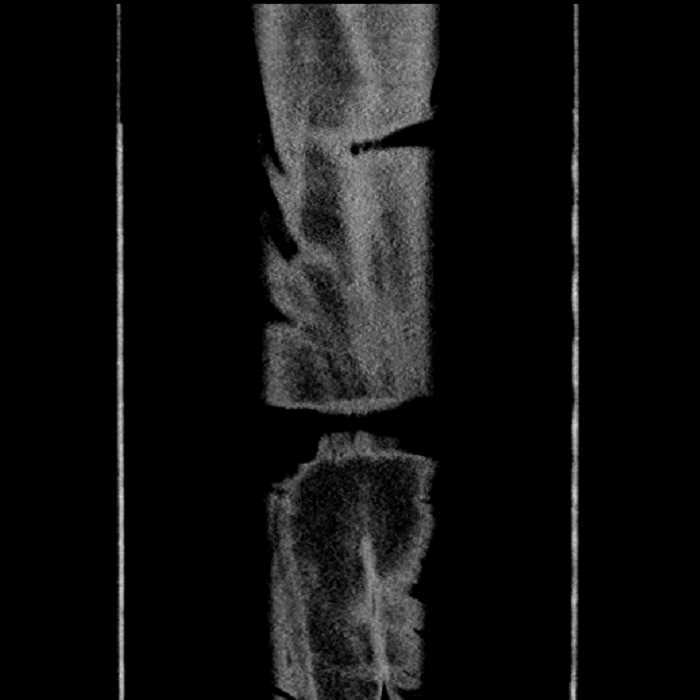

• Ankylosis of both sacroiliac joints

• Circumscribed sclerotic lesion in the left anterolateral seventh rib without aggressive features, likely a bone island